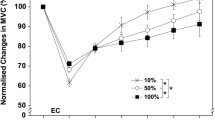

MVC torque and ROM

After CON, MVC torque decreased immediately (22.7 ± 13.0 %, p < 0.05) and 1 day (11.3 ± 7.6 %, p < 0.05) after exercise, but returned to baseline at 3-day post-exercise (Fig. 2a). After ECC, MVC torque decreased immediately after (32.7 ± 13.9 %, p < 0.05) and remained lower than the baseline at 1 (33.3 ± 12.6 %, p < 0.05) and 3 days (16.5 ± 9.7 %, p < 0.05) after exercise. MVC torque was greater for CON than ECC at 1, 3, and 5 days after exercise (p < 0.05). As shown in Fig. 2b, ROM decreased immediately post-exercise for both ECC and CON (p < 0.05), but decreases from the baseline at 1–5-day post-exercise were found only for ECC (p < 0.05). ROM was smaller for ECC than CON immediately, 1, 3, and 5 days after exercise (p < 0.05).

Changes (mean ± SD) in maximal voluntary isometric contraction (MVC) torque (a) and range of motion (ROM) (b) before (pre), immediately after (0), and 1, 3, and 5 days after concentric (CON) and eccentric (ECC) exercises. *Denotes a significant (p < 0.05) difference between CON and ECC. # Denotes a significant (p < 0.05) difference from pre-exercise value

Changes in MVC torque (Fig. 2a), ROM (Fig. 2b), and DOMS (Fig. 3) after ECC were comparable to those reported in the previous studies in which a similar eccentric exercise of the elbow flexors to that of the present study was performed (Chapman et al. 2006; Chen et al. 2009). The present study showed that brachialis CSA significantly increased from 1 to 5 days (25–35 %) after ECC, but this was not the case for CON, and no significant CSA increases were evident for biceps brachii and brachioradialis even after ECC. Nosaka et al. (2001) reported that brachialis was more damaged by eccentric exercise of the elbow flexors than biceps brachii. Kawakami et al. (1994) reported that brachialis contributed more (47 %) than biceps brachii (34 %) and brachioradialis (19 %) for the force production of the elbow flexors during isometric, concentric, and eccentric contractions. Therefore, the increase in brachialis CSA probably indicates that brachialis was more involved in ECC than the other two agonist muscles. This may explain why the increases in T2 at 1–5 days after ECC were greater for brachialis than biceps brachii.